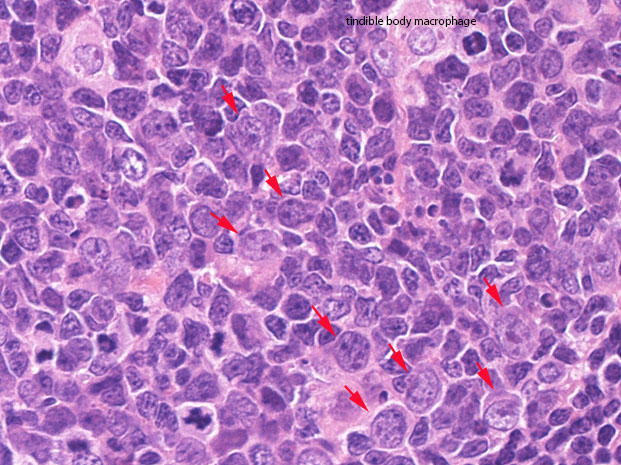

centrocytes(左図), centroblasts(中央, 赤矢印), Mantle zone-GC boder(右図) クリックで拡大図.

centrocyteはくびれや切れ込みのある核をもつ中から大型の細胞で核小体は明瞭なものと不明瞭なものがある.

centroblastは類円形大型のvesicularな核をもったN/C比大の細胞. 核小体が複数個核辺縁にくっつくように認められる.

胚中心には核分裂像やapoptosis像が多く, 正常胚中心のMIB-1 indexは高い。(FLでは low MIB-1 indexとなる. 後述)